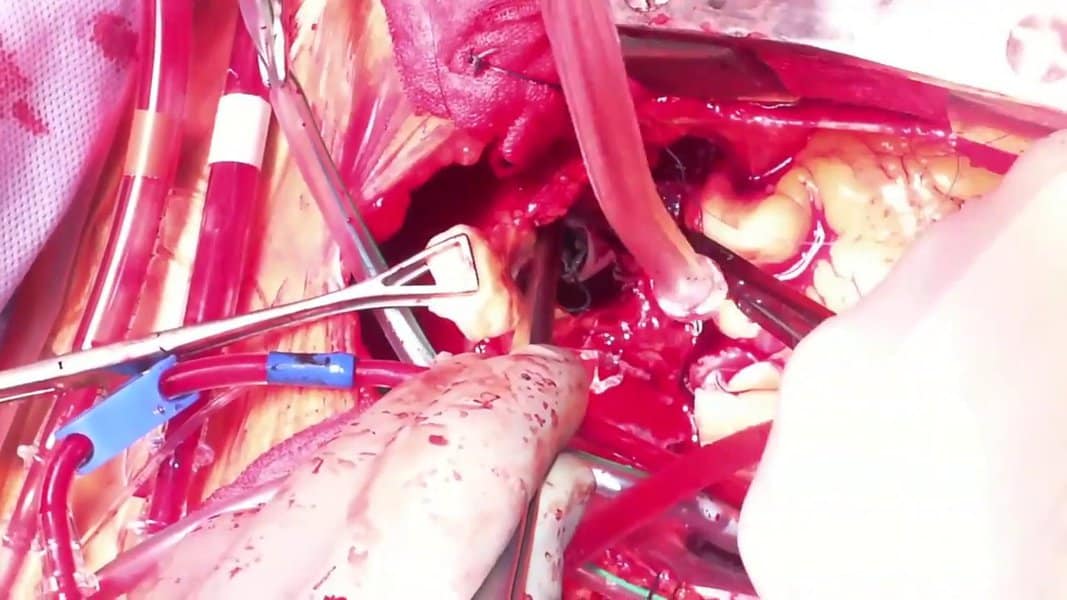

8. Small Bowel Resection

Small bowel resection is one of the most common emergency surgeries. The surgical procedure removes the diseased section of the intestine through two major surgeries. First, the removal of the small intestine is known as an enterectomy. On the other hand, a colectomy is the removal of the large intestine. Most patients require a bowel resection to treat GI cancer, a blockage in the intestine, or Meckel’s diverticulum.

The surgery can also help treat noncancerous tumors and inflammatory bowel disease. After the procedure, patients often suffer from the incision tearing open and intestinal bleeding. It can also result in an incisional hernia or intestinal blockages due to scar tissue buildup. In many cases, it’s a risky but necessary surgery.